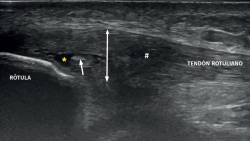

The ultrasound study of a damaged tendon evidences hypoechogenicity and loss of the fibrillar pattern, the appearance of disorganised connective tissue, and thickening of the tendon (Figure 3). In some cases we observe well delimited hypoechoic images indicating intra-substance rupture with nodular or fibrillar shapes, commonly manifesting in the deepest zone of the tendon in the lower pole adjacent to the patella (Figure 4).

Figure 4. High-resolution ultrasound study of patellar tendinopathy. Linear probe with longitudinal view. The double arrow shows increased tendon thickness, with hypoechogenic altered fibrillar pattern (#), intra-substance rupture (asterisk) and fibrosis (arrow).